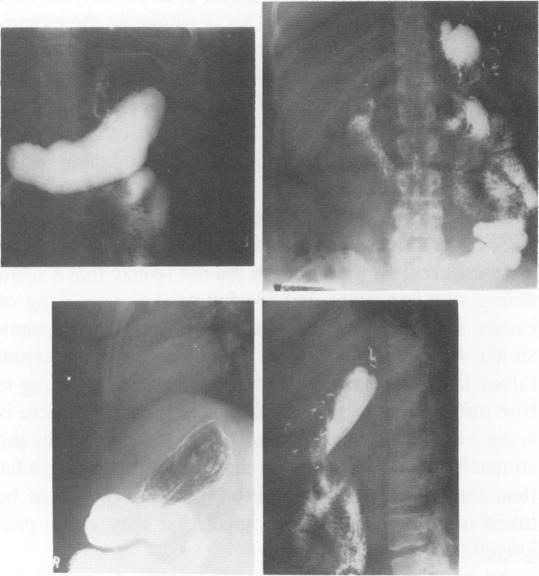

Gastric bypass is an extensive gastric exclusion operation used in patients who are more than twice their ideal weight. Most of the early postoperative deaths observed in 3% of 442 patients during the initial 9 years, could have been prevented by more attention to operative technique and early recognition and correction of leaks when they occurred. The best weight loss can be produced by adherence to three components of the operation: 1) Bypass of stomach and duodenum, 2) a small fundic segment and 3) a small (12 mm diameter) gastroenterostomy stoma. The average patient of 142 kg can expect to have a weight of around 107 kg at 1 year 103 kg at 5 years. Revision of a large stoma to a smaller (9 mm) diameter can induce further weight loss in some patients whose loss has been inadequate. The 1.8% incidence of stoma ulceration may be lowered with the present emphasis on a smaller fundic pouch, but could increase with longer observation. Presently stoma ulcers occur once in every 140 patient years at risk.